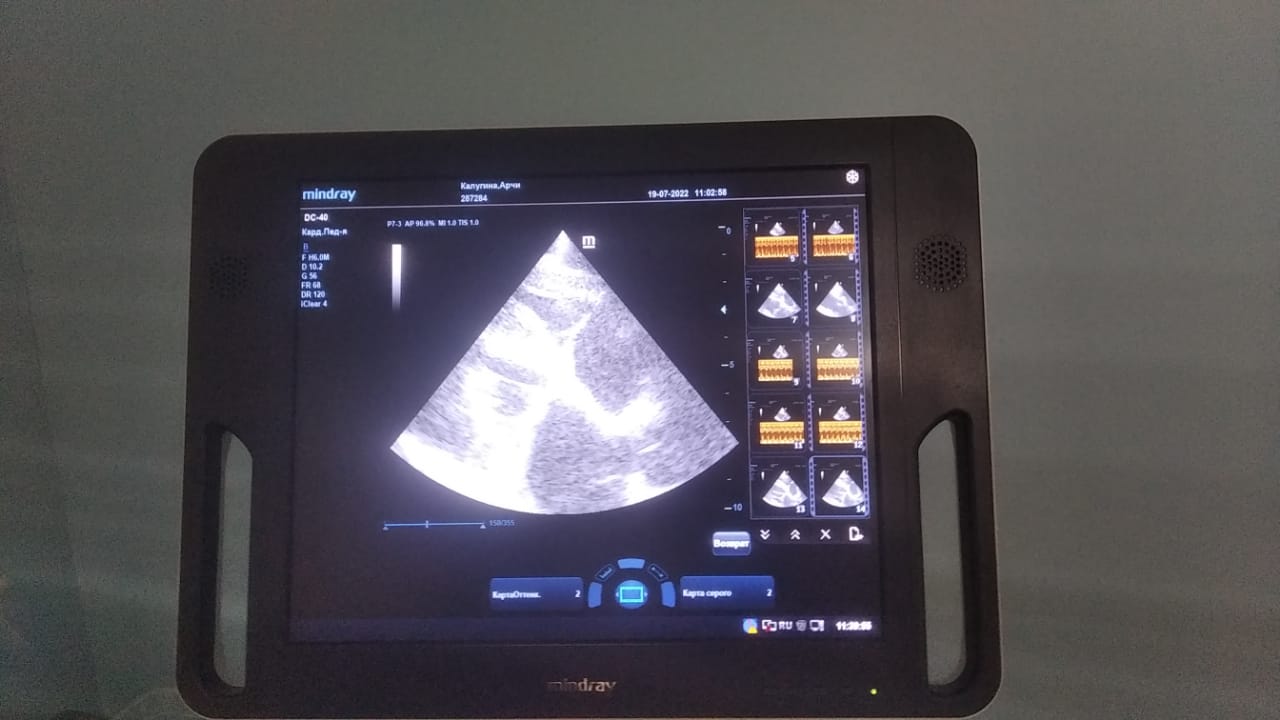

Анализы Арчи. Сердца и легких

Вложения

IMG-20220719-WA0100.jpg

IMG-20220719-WA0102.jpg

IMG-20220719-WA0104.jpg

IMG-20220719-WA0103.jpg

IMG-20220719-WA0105.jpg

Продолжение.